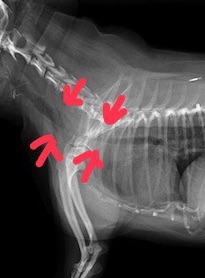

3歳チワワ、頸部気管虚脱

最近症例報告出来ていなかったので報告します。症例は3歳の若いチワワなのですがホームドクターで1歳の時にすでに気管虚脱と診断されています。初診時で頸部気管虚脱グレード3-4と診断しています。手術適応症例でした。またレントゲンでは後天的と思われる漏斗胸も確認出来ました。